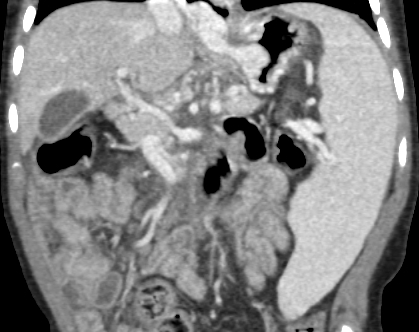

The patient underwent extensive workup for her suspected PHT. Computed tomography angiography (CTA) of the abdomen showed multiple small collateral vessels in the porta hepatis, compatible with cavernous transformation with absence of the portal vein (Figure 2).

Figure 2. Multiple small collateral vessels in the porta hepatis, compatible with cavernous transformation with absence of portal vein.